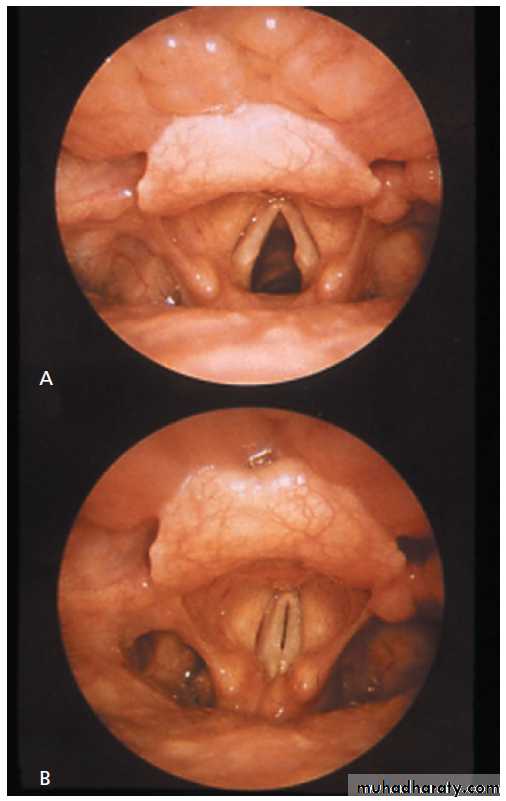

Laryngoscopic views of the vocal cords